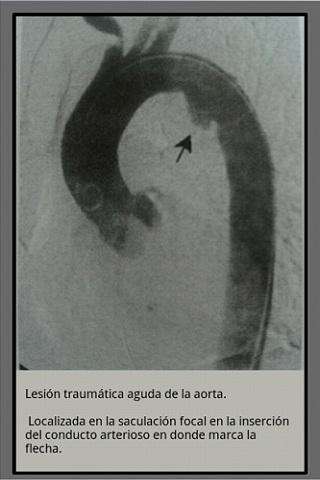

Hemos realizado una pequea coleccin de las radiografas bsicas presentes en los actuales exmenes de radiologa en medicina, fisioterapia y enfermera.

Sabemos que faltan muchas pero hemos puesto las que ms se han repetido en los exmenes que hemos revisado.